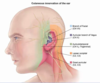

describe the innervation of the skin of the external ear

tympanic membrane and EAM sensory nerve supply

CNV3 (superior part of EAM and tympanic membrane) and CNX (inferior part of EAM and TM)

what is the lymphatic drainage of the lateral surface of the superior half of the auricle

parotid lymph nodes

what is the lymphatic drainage of the cranial surface of the superior half of the auricle

mastoid lymph nodes (purple) and deep cervical (light green)

what is the lymphatic drainage of the rest of the auricle, including the lobe

superficial cervical lymph nodes (dark green)

where does all lymph from the auricle eventually drain to

deep cervical lymph nodes (in carotid sheath), thoracic duct and then venous angle